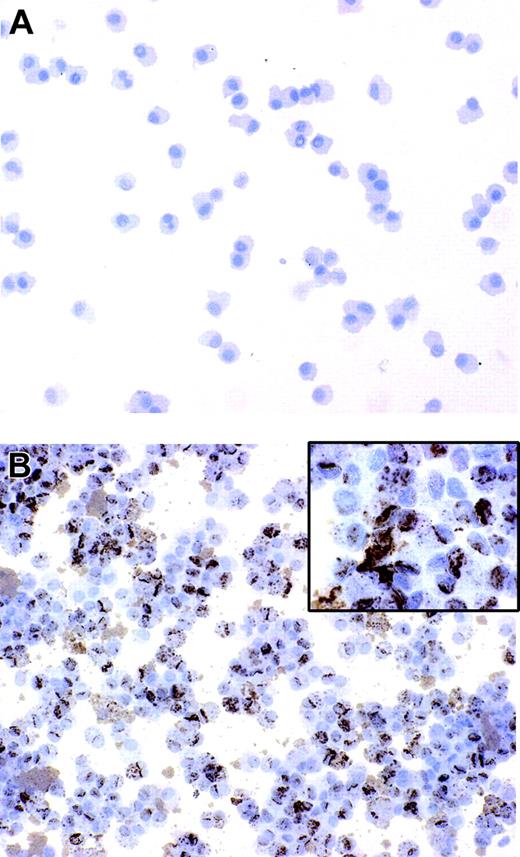

Immature DCs have an elevated intrinsic capability to internalize microbes and subsequently to differentiate into mature antigen-presenting cells.4  We have previously reported that B henselae is subjected to rapid internalization and survives in murine macrophages.25  In order to assess whether B henselae infects DCs, immature DCs were incubated with B henselae (bacteria/DC ratio 10:1) for 60 minutes. After gentamicin killing of extracellular bacteria, DCs were collected and subjected to cytospin and immunocytochemical staining by the use of anti–B henselae monoclonal antibody (anti-BH). We found that the majority of DCs (> 95%) that were incubated with bacteria were infected, as shown by the strong reactivity for anti-BH in their cytoplasm (Figure 1A-B). The staining was exclusively intracellular, with a granular cytoplasmic pattern of expression, suggesting that bacteria are internalized by DCs (Figure 1B inset).

Figure 1.

B henselae infects monocyte-derived DCs. DCs untreated or infected with B henselae were stained with anti-BH. No reactivity is detectable in uninfected DCs (A), whereas the majority of infected DCs display a strong positivity (B) with a granular cytoplasmic pattern (B inset). Immunoperoxidase technique for anti-BH counterstained with Meyer hematoxylin. Original magnification, × 200 (A-B) and × 600 (B inset).